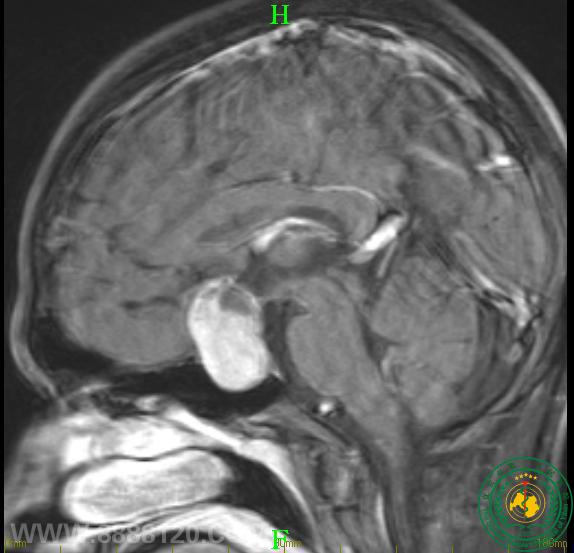

眼睛突然看不清,需警惕是颅内肿瘤作怪

眼睛突然看不清,需警惕是颅内肿瘤作怪15295